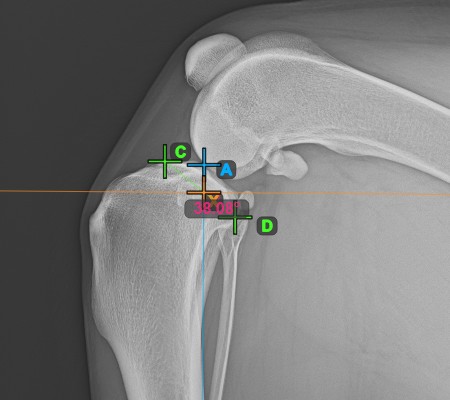

Continue by marking the midpoint of the Cochlea, located at the end of the tibial bone. The line created between the Eminentia Intercondylaris and the midpoint of the Cochlea represents the long axis of the tibia.

The image below depicts the usual placement of the midpoint of the Cochlea.

Once the long axis of the tibia has been identified, mark the most cranial point of the tibial head (tibial plateau).

The image below depicts the usual placement of the most cranial point on the tibial plateau.

Complete the TPA Angle measurement by marking the most caudal point of the tibial head (tibial plateau). The TPA Angle is automatically calculated as the angle between the line connecting the two points on the tibial plateau and the perpendicular line to the long axis of the tibia.

The image below depicts the usual placement of the most caudal point on the tibial plateau and the automatically calculated TPA Angle measurement.